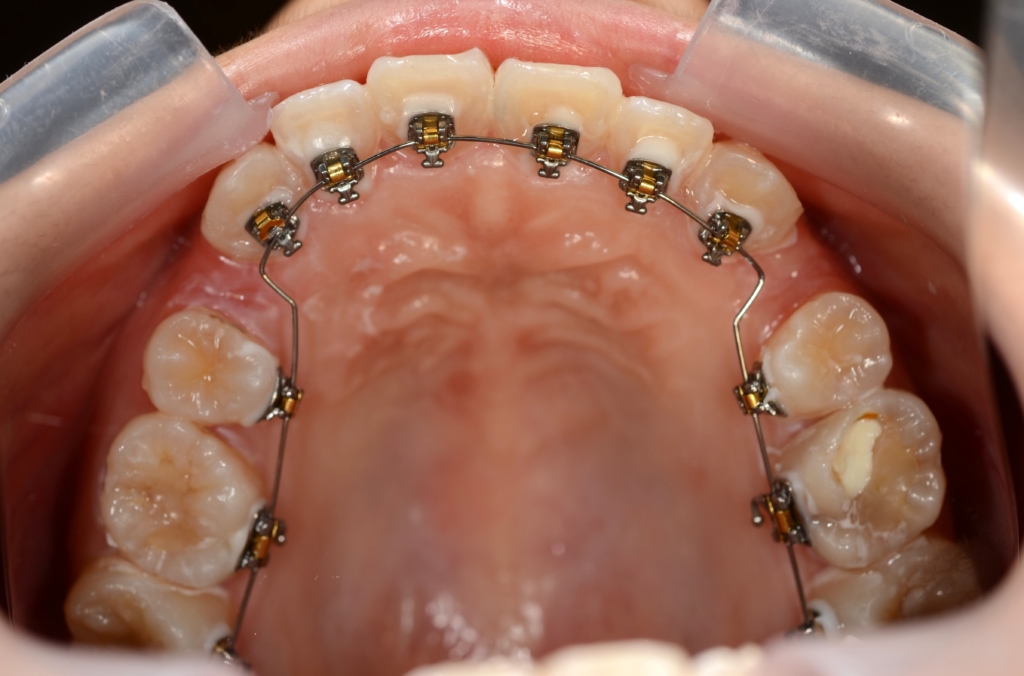

マルチブラケットシステム(ハーフリンガル type)で矯正を開始。

上下の左右の奥歯を1本ずつ計4本抜歯(4番目の第一小臼歯を抜きました)

(上顎の智歯は出来るだけ早期に抜歯を予定しています。

左下奥の横になって埋っている智歯は様子見です)